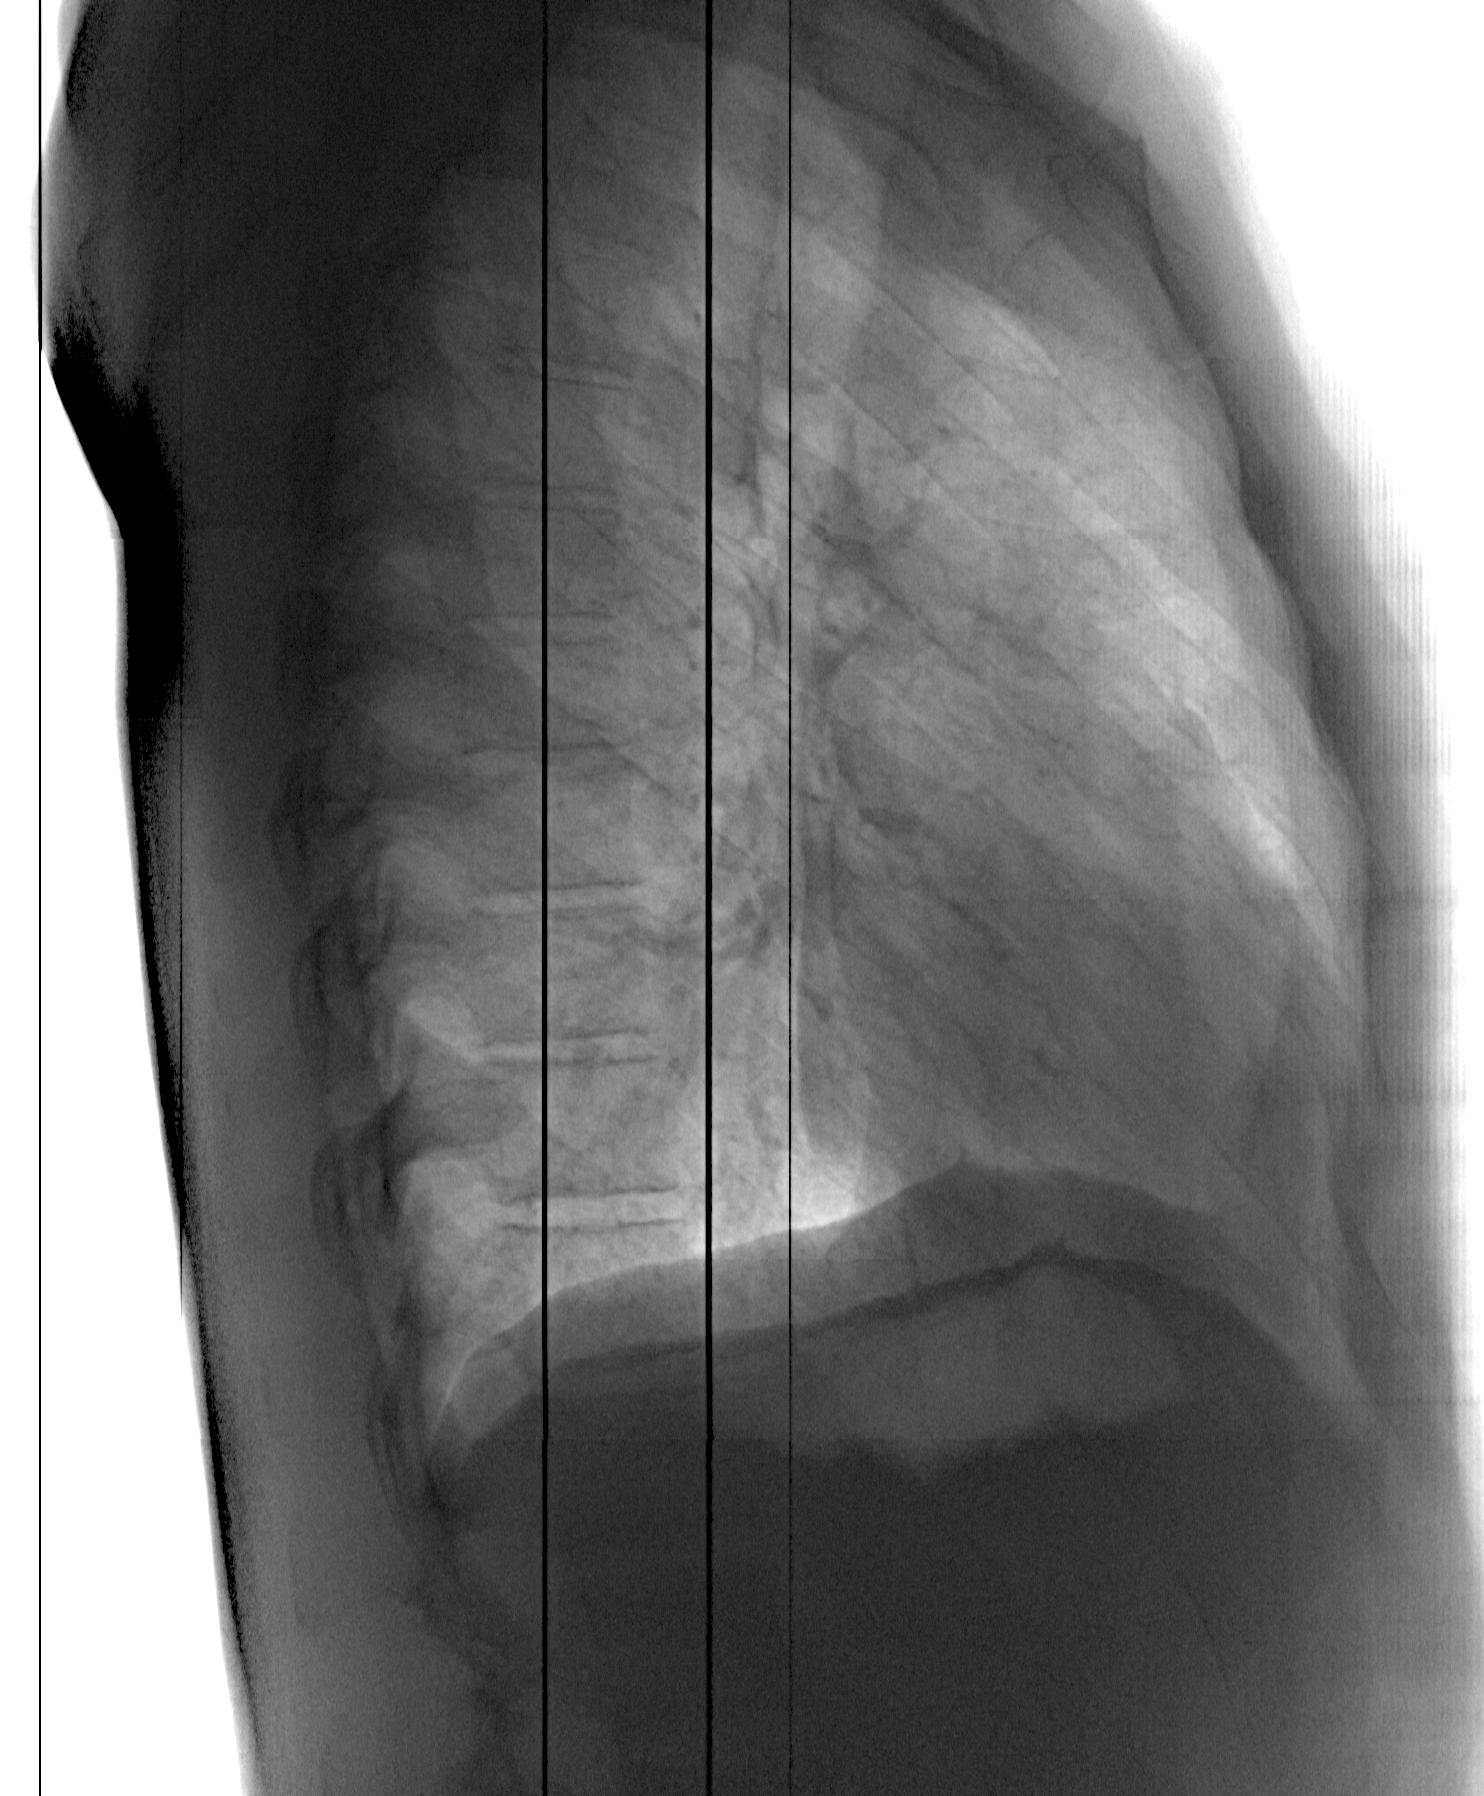

Пациент 1991г.р. Тень в мягких тканях слева (возможно на лопатке?)... если на коже - то понятно, если нет, то что это? Архив с разницей в полгода.

Папиломма или невус скорее всего

Кальцинированный подмышечный лимфоузел, может быть.Надо осмотреть пациента глазами, принеобходимости-скопия.

Скорее всего кальцинированный лимфоузел. возможно после жолодного абсцесса в дремучем детстве :-) его и прощупать при желании можно

рубчик БЦЖ на плече надо глянуть

Минерализованый л\узел...рядовое явление.....можно с десяток разновидностей наблюдать...если не больше))))

Согласен с калицинированным лимфоузлом